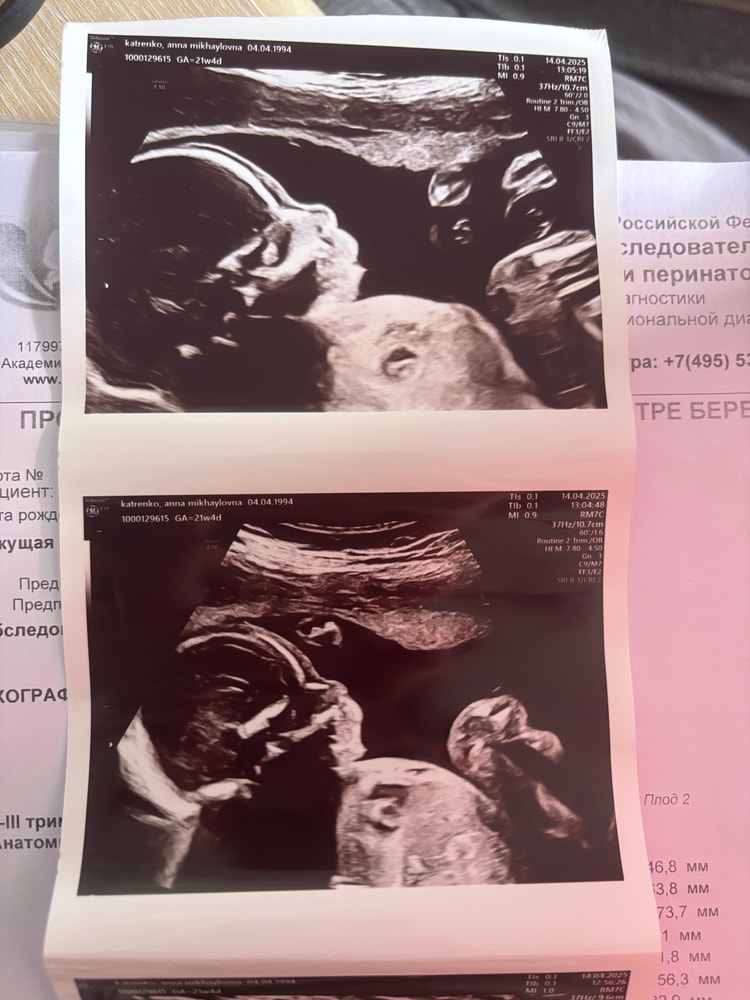

Изображение Изображение